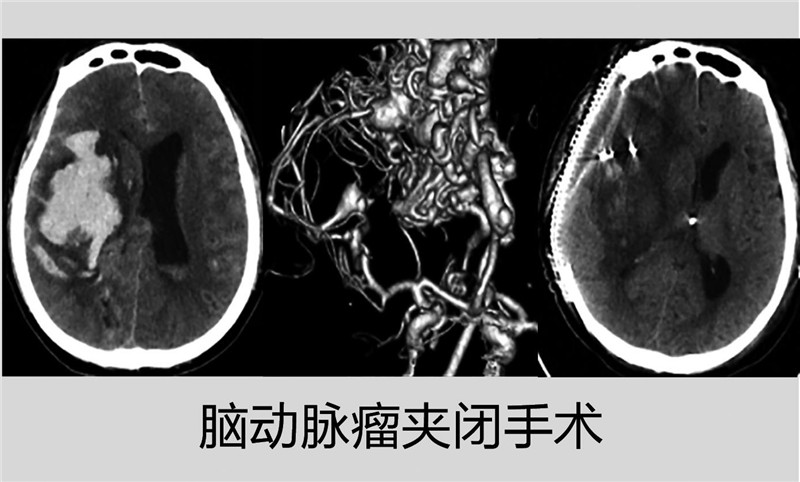

另一例突发脑出血深昏迷的患者76岁,被诊断为脑内巨大血管畸形合并脑动脉瘤破裂出血,该科急诊手术清除了脑内血肿,同时给予动脉瘤夹闭治疗,使危在旦夕的老人保住了性命。手术后患者又历经肺部感染、多次心衰、电解质紊乱等继发病症的综合性治疗后才完全苏醒,此后又因其继发性脑积水,医生再次给予完成脑积水分流及颅骨修补手术;治疗共历时两个月,使患者达到言语交流无碍、能在搀扶下完成基本的生活。